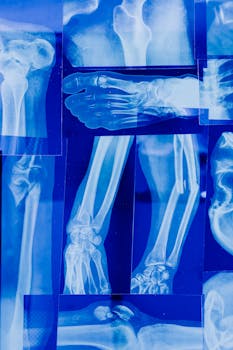

Osteopenia is a condition characterized by lower than average bone density, often seen as a precursor to osteoporosis. This naturally raises the question: can osteopenia be reversed? While complete reversal may not always be possible, there are steps you can take to improve bone density and prevent further bone loss. A combination of lifestyle adjustments, dietary choices, and healthcare guidance plays a vital role in managing osteopenia effectively.

Osteopenia involves reduced bone mass, making bones weaker and more susceptible to fractures. This condition often goes undetected until a bone density test reveals it. Unlike osteoporosis, osteopenia doesn’t always lead to frequent fractures but does increase the risk if not addressed. For many, the goal is to halt progression and maintain bone strength through various interventions.